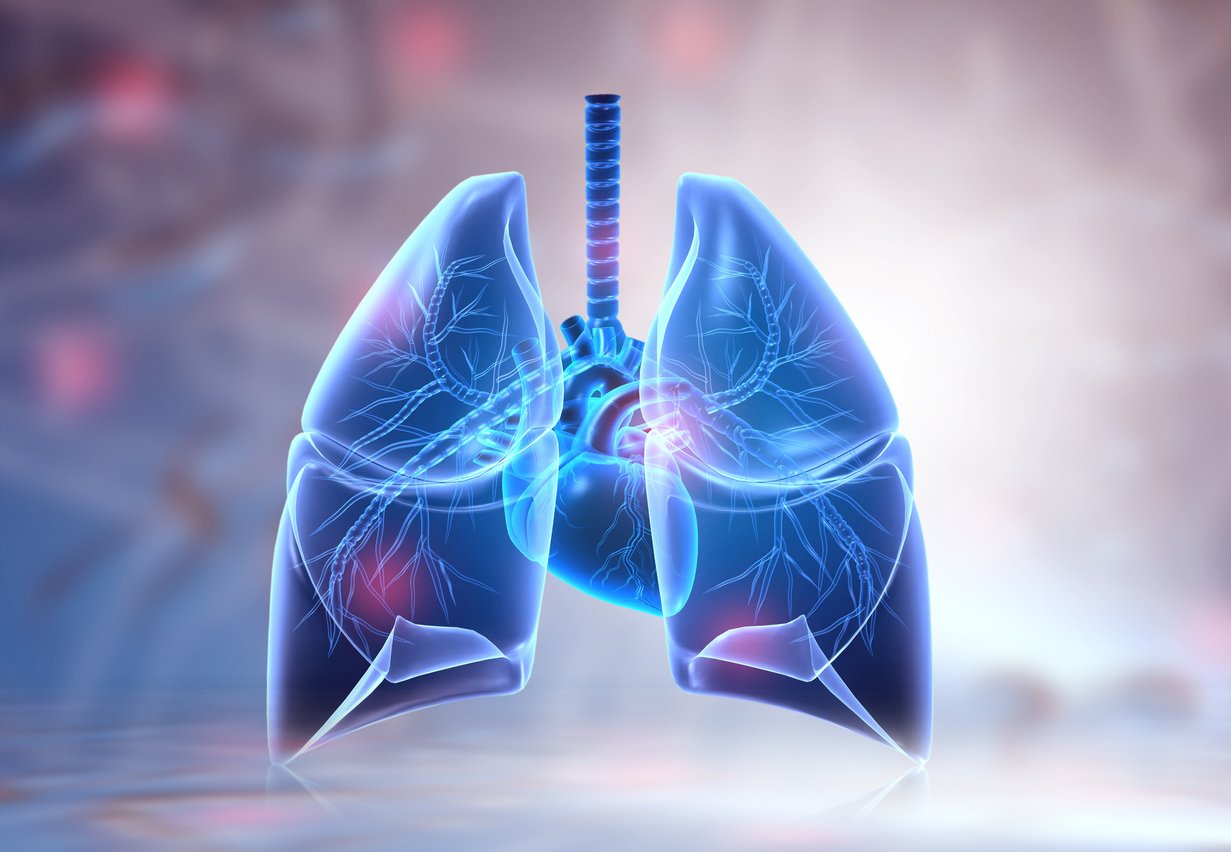

Лёгкие человека: Учебные картинки для детей